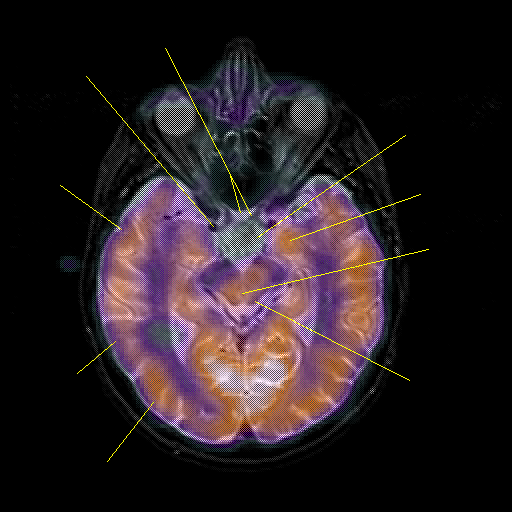

overlay : Slice 23

Slice 23

Pointers

Labeled